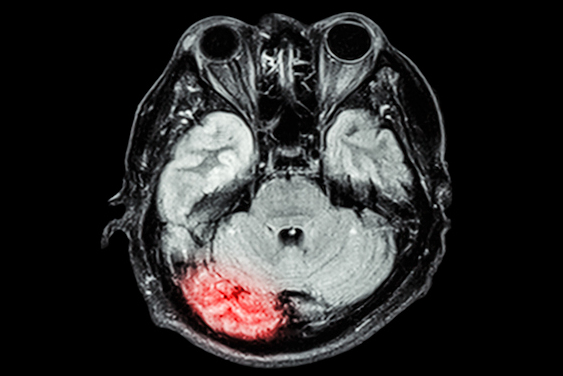

Grundinger and colleagues sought to better understand the "rewarding properties" of e-cigarettes and to compare their use to tobacco cigarettes via a study that explored the addictive potential of e-cigarettes and implications for smoking cessation. The study included 47 daily e-cigarette users -- 43 of whom were former tobacco smokers. Of the study participants, 32 used e-cigarettes exclusively, while 15 used both e-cigarettes and tobacco cigarettes; all underwent functional MRI. The investigators tracked each person's "anticipatory brain activation to reward-predictive stimuli for money, e-liquid, or tobacco cigarettes."

They found the following:

- Increased activation in the participants' limbic regions (i.e., the nucleus accumbens) prompted by anticipation of receiving e-liquid and money over tobacco cigarettes in exclusive e-cigarette users. The nucleus accumbens controls motivation and reward.

- Greater activation in prefrontal brain regions prompted by anticipation of money compared to e-liquid or tobacco cigarettes. These regions control decision-making, reasoning, personality, social appropriateness, executive function, and attention and focus.

- Greater activation for money compared to tobacco cigarettes in the hippocampal limbic systems of dual users. This area of the brain controls emotions and behavioral responses.